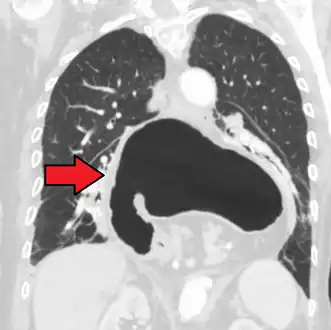

A hiatal hernia as seen on CT

A large hiatal hernia as seen on CT imaging